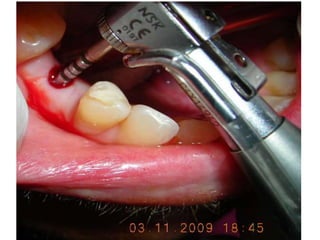

•Strictly following the basic fundamental surgical protocol

for one-stage one-piece implant

•Bone drilling at a very very low speed

Favorable implant-bone interface:Attributed by……. •Strictly following the basic fundamental surgical protocol for one-stage one-piece implant •Bone drilling at a very very low speed •Use of surgical tap in D1 & D2 type of bone •Immediate temporaries: out of occlusion